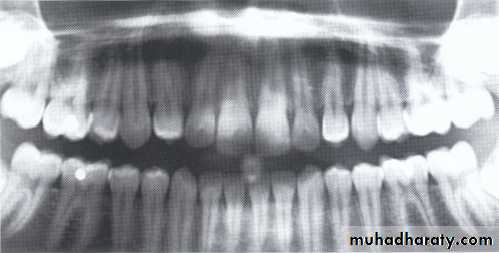

Developmental absence of all maxillary premolars and both mandibular second premolars. Note the retention of the maxillary primary canine as a result of the posterior position of the maxillary permanent canine.

CAUSES: may be the result of numerous independent pathologic mechanisms that can affect the orderly formation of the dental lamina (e.g.,orofaciodigital syndrome), failure of a tooth germ to develop at the optimal time, lack of necessary space imposed by a malformed jaw, and a genetically determined disproportion between tooth mass and jaw size.

*Mild hypodontia by orthodontics.

*Severe cases by restorative, implant, and prosthetic procedures .